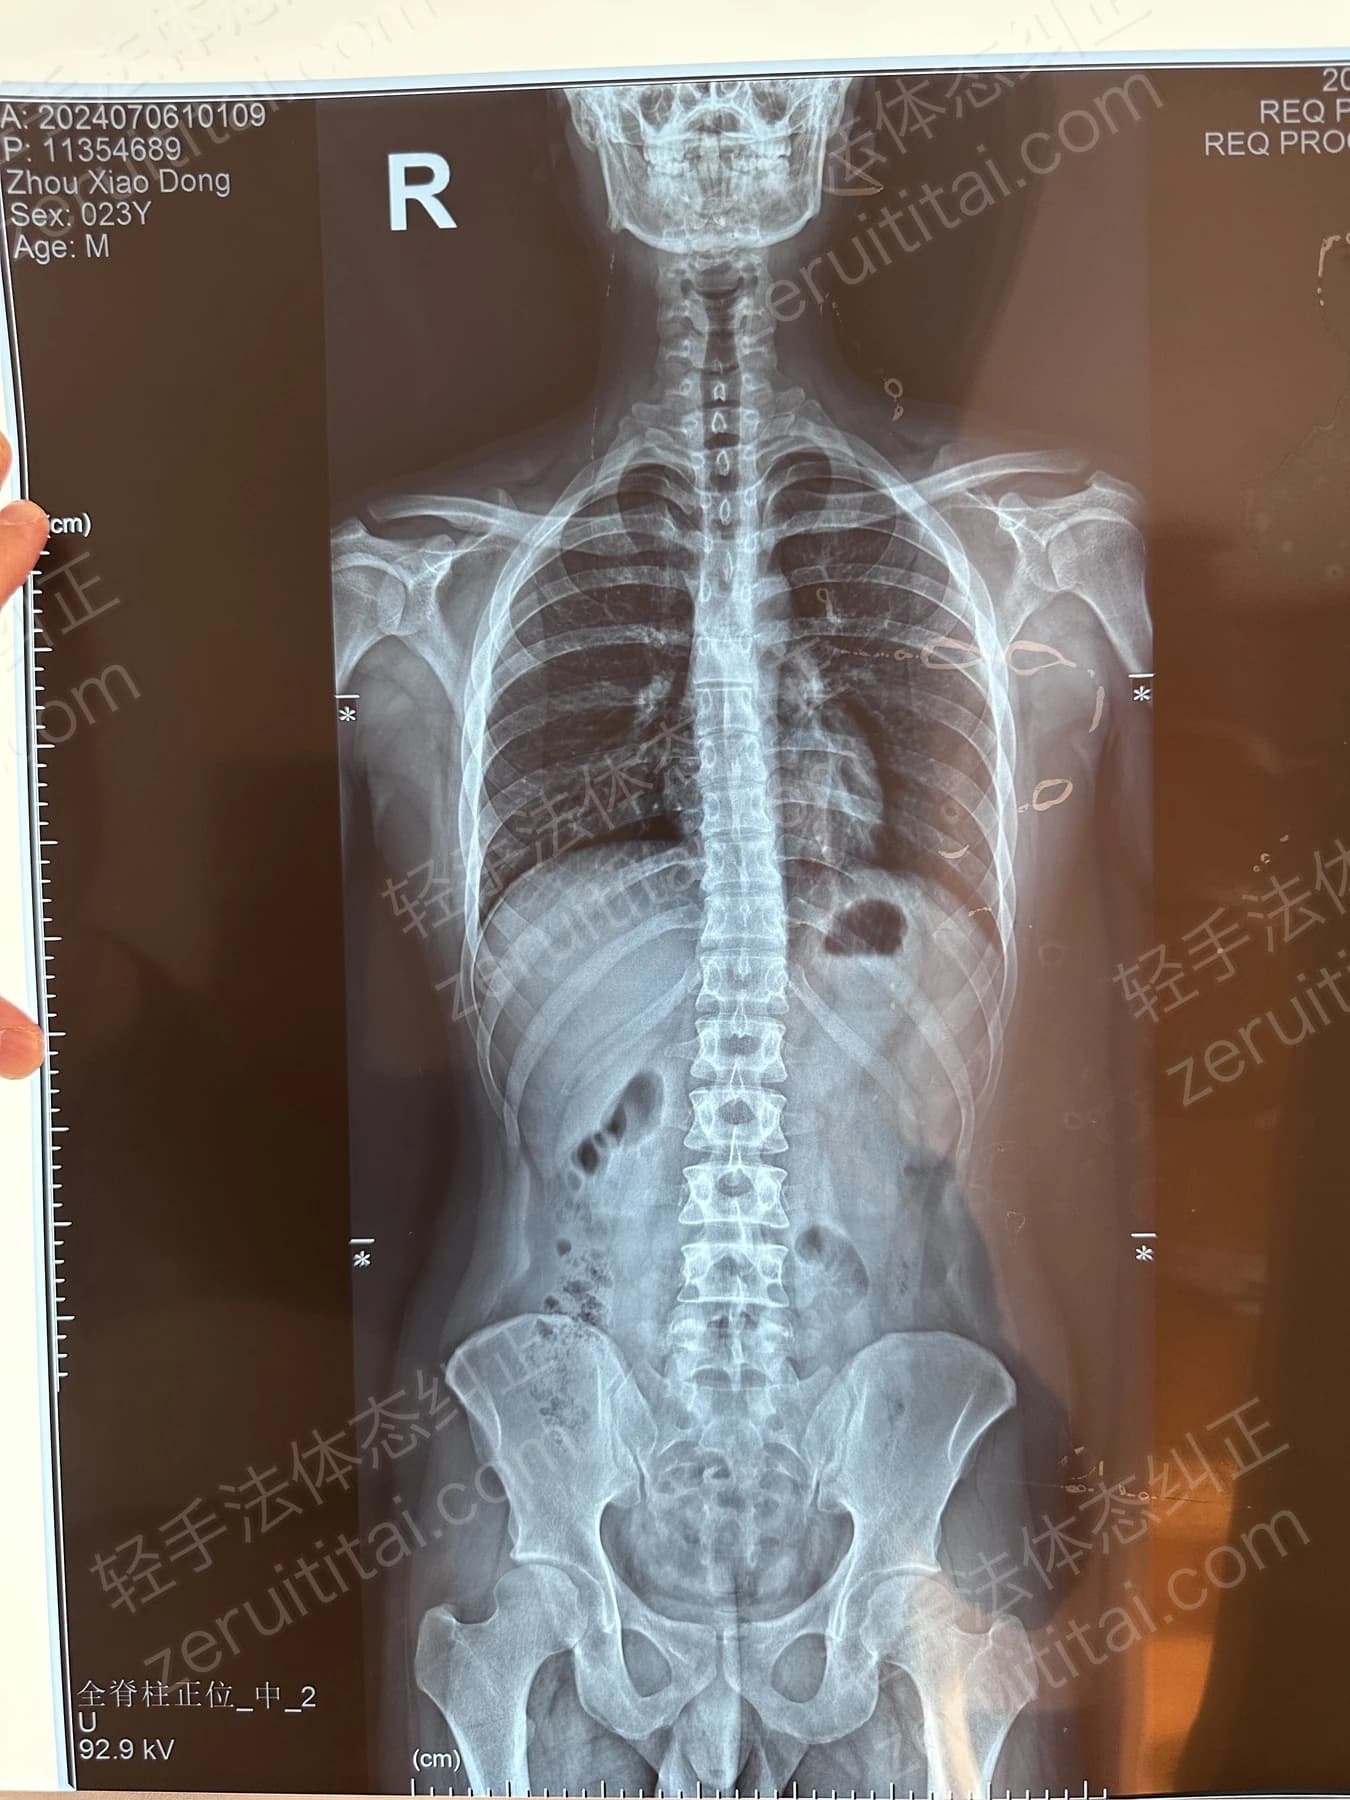

2023.05.30

第 4 次记录